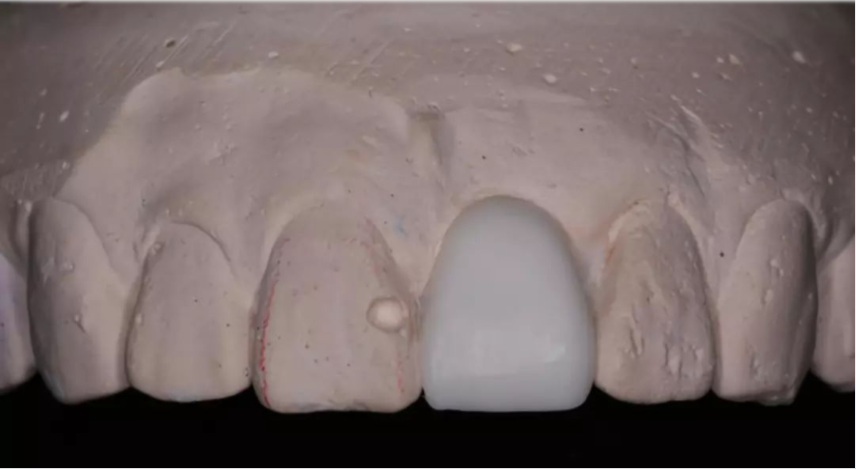

術(shù)前制取參考模型,排美學蠟型,實現(xiàn)以美學修復(fù)為導(dǎo)向的種植

設(shè)計軟件中,選擇適合的種植體

根據(jù)修復(fù)體形態(tài),軸向以及骨量將種植體放置最適合的位置